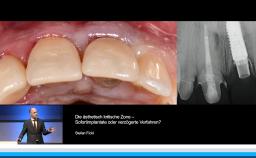

Basierend auf diversen Studien und eigener klinischer Erfahrung stellt Dieter Weingart seine Erkenntnisse und Schlussfolgerungen zum Thema Implantatverlust mit Defektbildung vor. Er illustriert das Thema mit eigenen klinischen Fällen inklusive Langzeit-follow-ups.

- die Empfehlung einer erneuten implantologischen Versorgung nach Implantatverlust mit Defektbildung diskutieren können

- Erfolgs- und Risikofaktoren einer erneuten Implantation benennen können